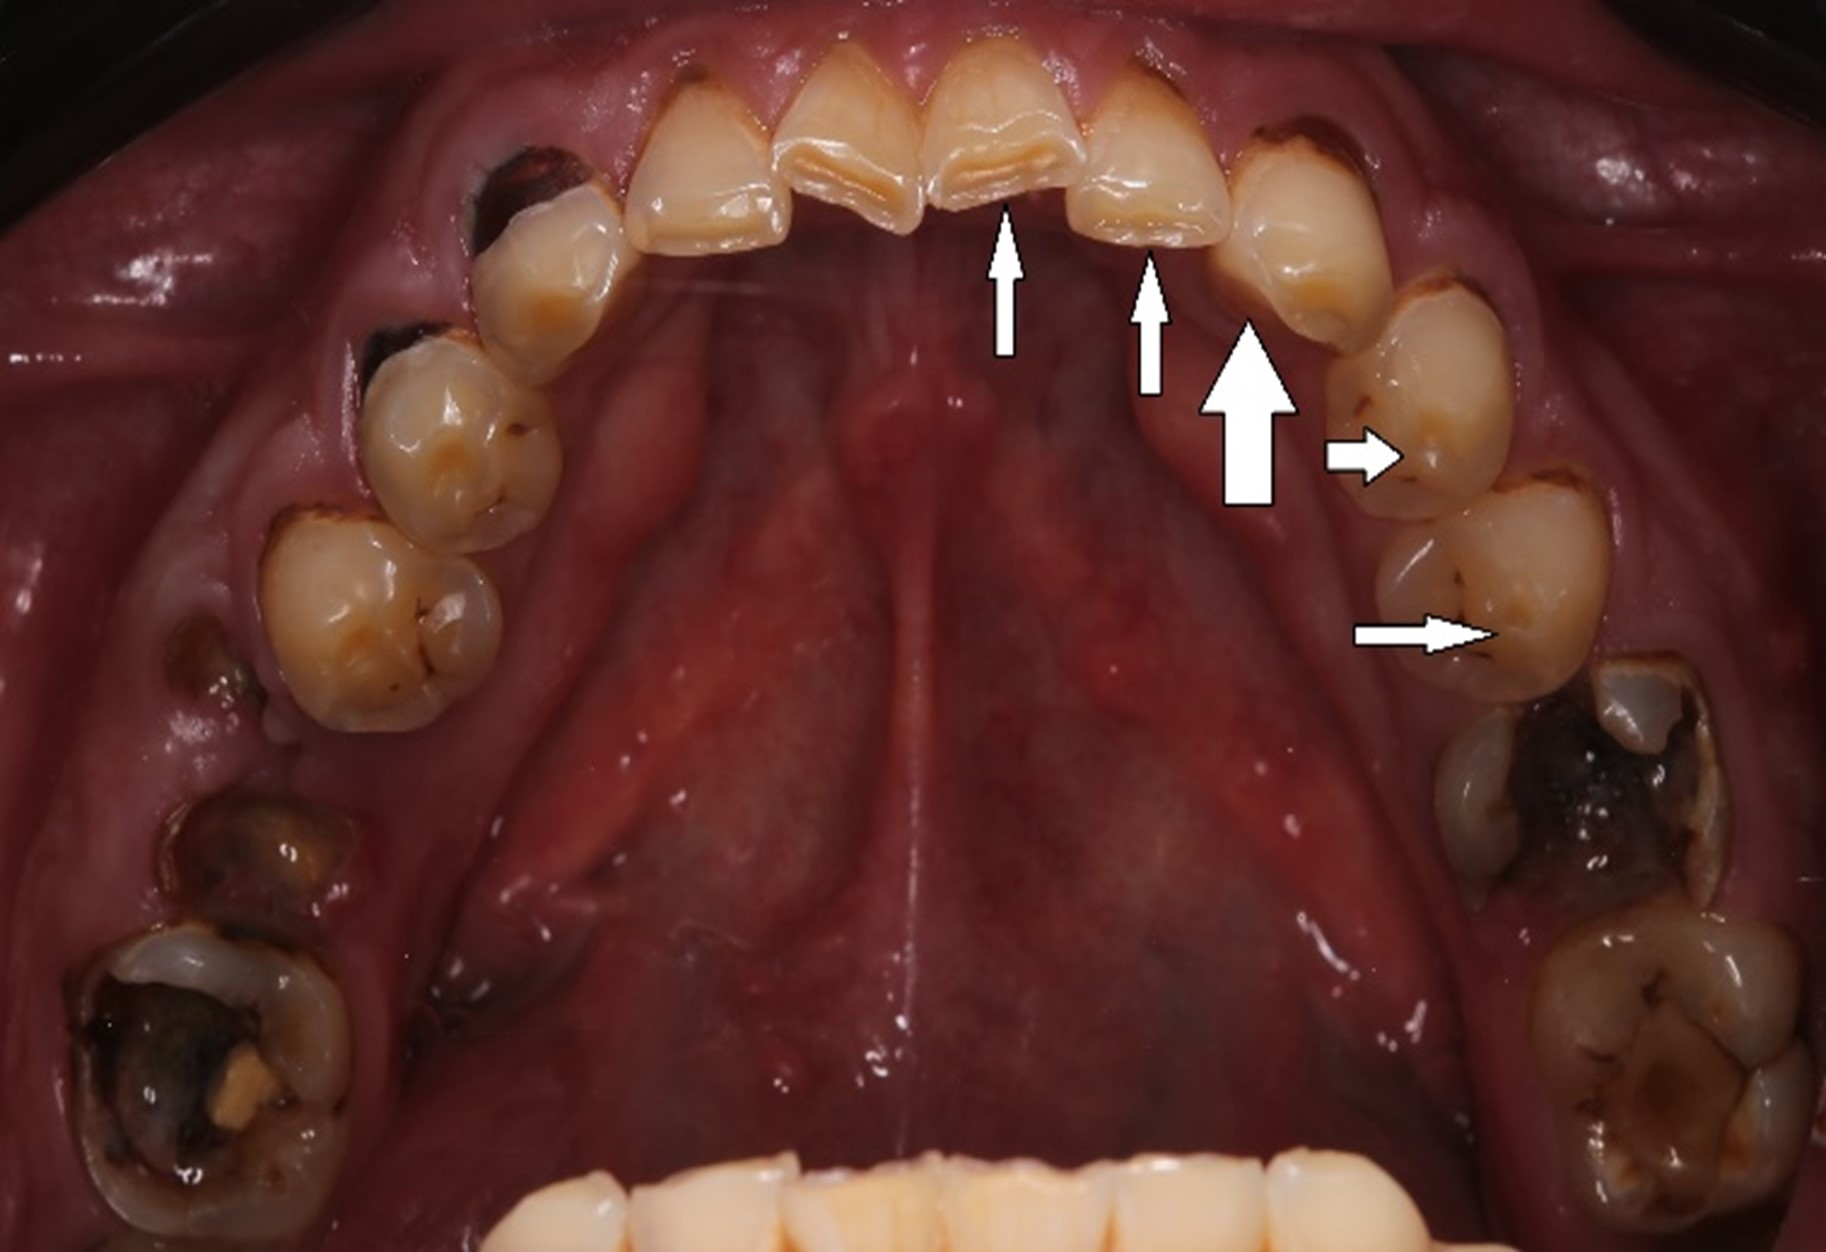

Напоминаю: он пришёл к нам вот в таком состоянии:

На нижней челюсти у него жевательных зубов не было вообще:

С верхней было немного получше, но не так чтобы сильно:

Жалобы были не только на внешний вид зубов, но ещё и на проблемы с дыханием и приёмом пищи. Общаться с людьми было тоже некомфортно.

Во-первых, нам нужно было сохранить как можно больше живых зубов при условии, что ни одного целого не было: везде либо вторичный кариес под пломбами, либо сколы, либо стёртые зубы, либо сильно разрушенные. А на фронтальной группе — всё это сразу.

На первом приёме я внимательно смотрю на фотографию. Глаз у меня уже намётан, так что буквально за полминуты можно увидеть следующее.

В жевательном отделе зубов практически нет. На зубах с первого по пятый появились небольшие фасетки стираний, которые означают, что прикус зафиксирован именно на них. Если они настолько отчётливые, как у Ивана, это значит, что зубы начинают стираться, и высота нижнего отдела лица уменьшается. Значит, придётся повышать прикус, чтобы вернуть височно-нижнечелюстной сустав и зубы в первоначальную здоровую позицию. Это будет моей задачей.

Такие разрушенные зубы, заросшие десной, кричат о необходимости имплантации

Кариозные процессы сигналят о терапевтической реабилитации и терапевтической санации полости рта

Воспалённые дёсны намекают на пародонтологию